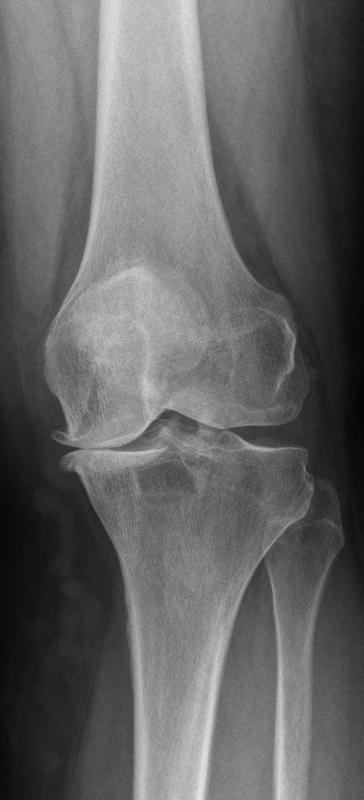

Rund fünf Millionen Menschen in Deutschland leiden nach aktuellen Schätzungen an einer Arthrose. Die Gelenkerkrankung betrifft vor allem Knie, Hüften und Hände. Zu ihren Kennzeichen gehören die fortschreitende Zerstörung der Knorpelschicht eines Gelenks und damit einhergehende Veränderungen der angrenzenden Knochen. Das Gelenk entzündet sich und schwillt an; der betroffene Patient leidet unter teilweise heftigen Schmerzen und kann sich nur schlecht bewegen.

Sechs Patienten haben die Mediziner in Würzburg und Montpellier inzwischen auf diese Weise behandelt. Bei allen war die Krankheit schon so weit fortgeschritten, dass der OP-Termin schon feststand, an dem sie ein künstliches Gelenk erhalten sollten. Die Ergebnisse der Stammzell-Therapie sind vielversprechend: „Über die ersten drei Monate hinweg geben alle Patienten an, dass sie seit der Stammzell-Injektion deutlich weniger Schmerzen verspüren als zuvor“, sagt Professor Nöth. Auch ihre Mobilität habe deutlich zugenommen: Viele gingen wieder einkaufen, selbst Treppensteigen ginge wieder besser – alles Tätigkeiten, zu denen sie vorher nur bedingt in der Lage gewesen seien. Insgesamt berichten die meisten, dass sich ihre Lebensqualität verbessert habe.

Wie im Detail die Stammzellen diese Veränderungen bewirken, ist derzeit noch unklar. „Wir wissen nur, dass die Zellen gegen den Entzündungsreiz wirken und damit die typischen Symptome deutlich lindern“, sagt Nöth. Eine schützende Knorpelschicht neu bilden: Dazu seien die Zellen wahrscheinlich nur teilweise in der Lage. Aus diesem Grund hält der Mediziner die Stammzelltherapie eigentlich für einen anderen Kreis von Patienten für geeigneter: Patienten im Alter zwischen 40 und 50 Jahren mit einer moderat ausgeprägten Arthrose – „zu jung für eine Prothese und zu alt für eine Knorpelzelltransplantation“, wie Nöth sagt. Bei ihnen könnte die Gabe von Stammzellen den Zeitpunkt, zu dem ein künstliches Gelenk fällig wird, signifikant nach hinten schieben.

Zwei Millionen mesenchymale Stammzellen haben die ersten sechs Teilnehmer der Studie in das Kniegelenk verabreicht bekommen. Nachdem sie diese Behandlung ohne Komplikationen überstanden haben und unerwünschte oder unerwartete Ereignisse ausgeblieben sind, dürfen die Mediziner bei den nächsten sechs die Dosis steigern: Dann wird die Spritze zehn Millionen Zellen enthalten. Läuft auch in diesem Fall alles problemlos, erhält das dritte Drittel der Studienteilnehmer die maximale Dosis von 50 Millionen Zellen. Bis Ende 2013 sollen die Ergebnisse dieser Phase-1-Studie vorliegen.